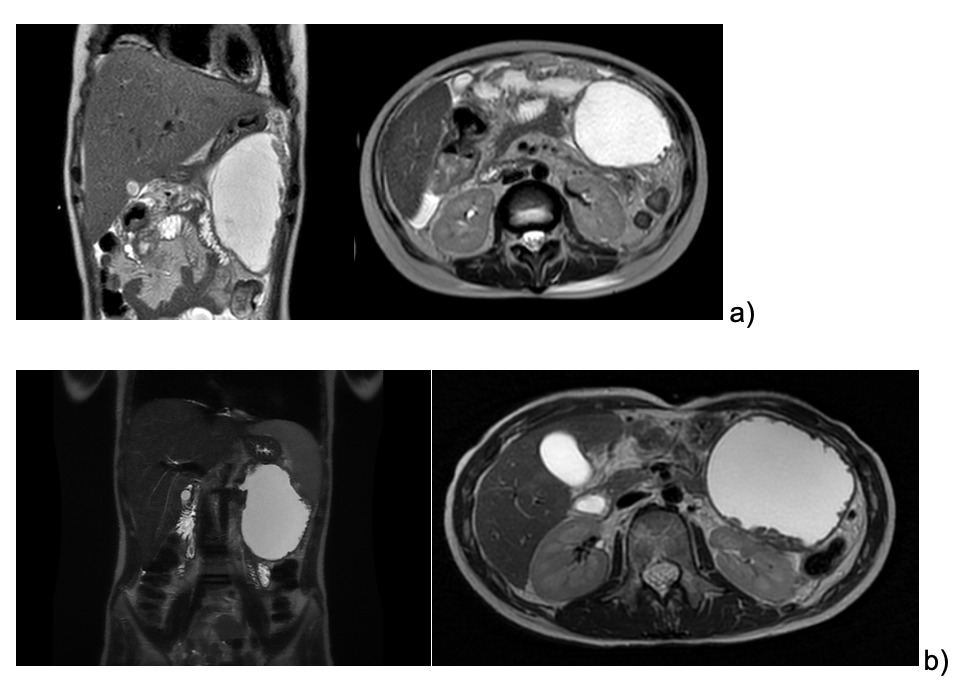

The patient continued to refer mild abdominal pain, and a cholangio MRI confirmed the persistency of an encapsulated pancreatic fluid collection without size reduction (Fig.1b). After a multidisciplinary discussion, the decision was made to perform an endoscopic-ultrasound (EUS) guided cystogastrostomy with a 10 x 10 mm lumen-apposing metal stent (LAMS) (Hot-Axios™ system) under general anesthesia. During the procedure, after the release of the LAMS, a 7 cm x 7 Fr double-pigtail plastic stent (DPPS) was coaxially released (Fig.2); the post-operative course was uneventful and the patient was discharged after 48 hours. Seven days thereafter, an abdominal ultrasound confirmed the complete resolution of the PCF, the LAMS was removed, and a “soft” DPPS 7 cm x 10 Fr (Solus-Cook®) was positioned endoscopically in the cystic cavity under endoscopic and radiological control (Fig.3). The patient was dismissed the following day without any complications, and two weeks thereafter she restarted the AIEOP-BFM-2017 protocol at Short Consolidation B, 4 months after the interruption of the consolidation phase. No pancreatic fluid collection was observed at the following abdominal ultrasounds, the latest performed 7 months after interventions, together with an abdominal x-ray that showed the persistent presence of the double pig-tail. The prosthesis removal will be scheduled together with the central venous catheter removal at the end of the maintenance phase, due in a few months, so as to perform a single sedation.

_echoendoscopy__b-c)_stent_placement.png)

_dpps_positioning__b)_radiological_control.png)